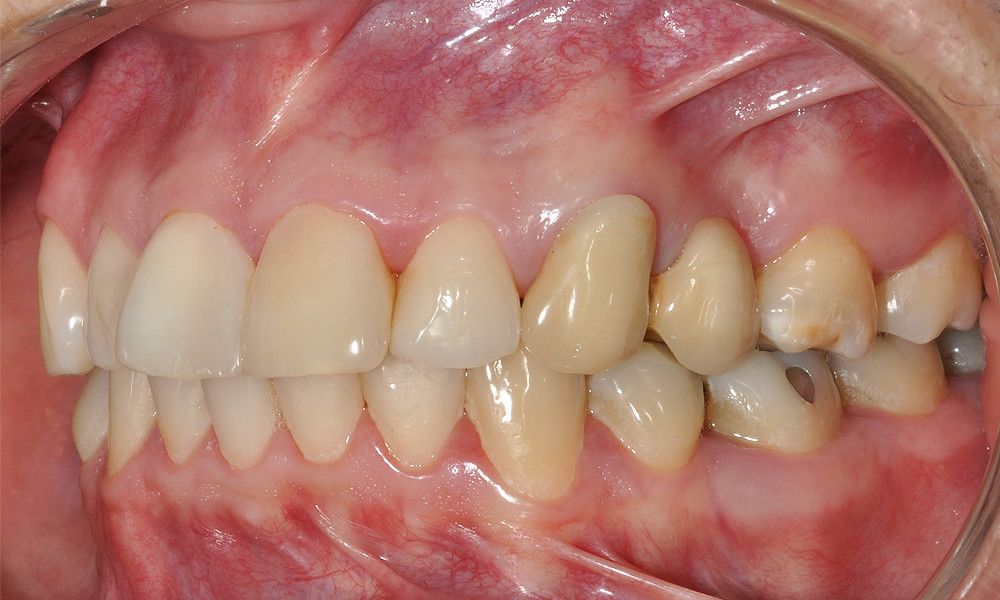

Reporte del Caso: Paciente sexo masculino, 36 años, con diagnóstico de esquizofrenia y trastorno bipolar en tratamiento. Consulta por el recambio de dos prótesis fijas plurales (PFP) de reemplazo de dientes 4 y 13 con pilares en piezas 3, 5, 12 y 14 mediante rehabilitaciones unitarias de los dientes pilares y reemplazo mediante implantes en zonas edéntulas.

El estudio imagenológico evidencia una pérdida ósea severa en altitud y grosor, situación que complejiza la colocación de un implante. Se analizan alternativas de tratamiento y se opta por una vestibuloplastía mediante autoinjerto conectivo de mucosa palatina que se reposiciona sobre la zona del defecto óseo. Además se realiza retratamiento de ambas PFP, ahora en zirconia, por motivos estéticos y oclusales. Se realizan controles posteriores para evaluar la respuesta gingival a la vestibuloplastía.